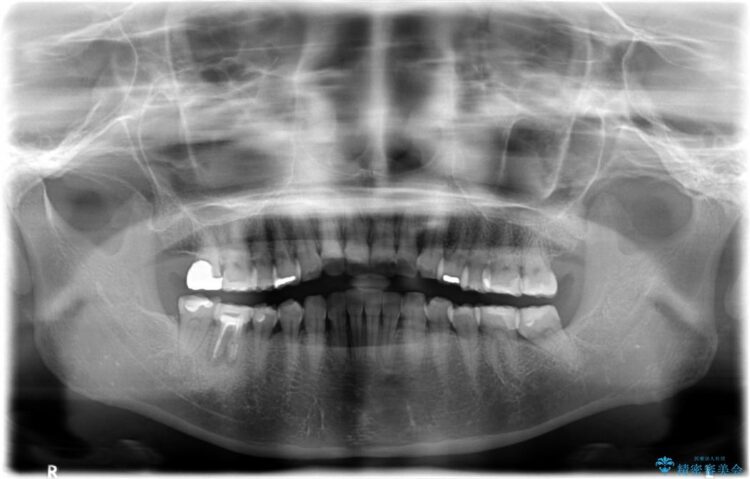

他院で右下の奥歯を抜歯しなければならないと言われ、当院へ相談に来られました。

治療計画

精密な検査を行ったところ、根が完全に折れている為、抜歯が必要となりました。抜歯後は骨と歯茎が痩せてしまう事がないように、人工の骨をつめ、インプラント治療を行う計画としました。